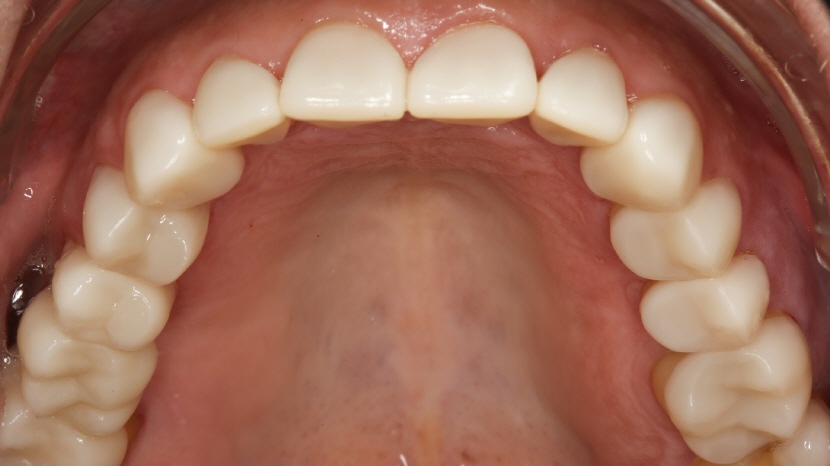

• Aufbissansicht des Oberkiefers

Deutlich sichtbarer, generalisierter Schmelz- und Dentinverlust.

• Oberkiefer Front:

Wie alle Cerec-Rekonstruktionen wurden ebenfalls die Frontzahnkronen in einer Sitzung hergestellt, poliert und mit lichthärtendem Komposit (GC G-Aenial Universal Injectable A1) eingesetzt.